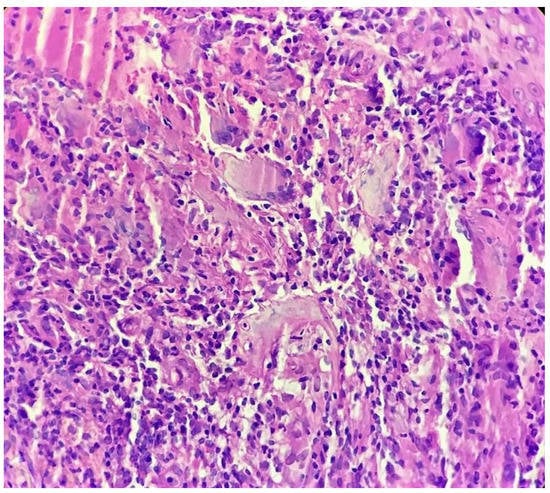

Biopsy showed a dense lichenoid and loose tuberculoid granulomatous infiltrate comprising of epithelioid cells, histiocytes and occasional Langhan’s giant cells, surrounded by lymphocytes and few plasma cells. The granuloma was seen abutting the overlying epidermis, which showed psoriasiform hyperplasia with mild to moderate spongiosis. A compact tuberculoid granuloma was also seen in the deep reticular dermis. Fibroplasia was also seen in the dermis (Figure 2, Figure 3, Figure 4 and Figure 5). The PAS-stained sections were negative for fungal organisms. Zeil–Neelsen stained sections did not reveal any acid-fast bacillus. Based on these features, a diagnosis of lupus vulgaris was favoured and further confirmation by culture study and PCR was advised.

Figure 4. Tuberculoid granuloma in upper dermis comprised of epithelioid cells, giant cells and surrounded by lymphocytes (H&E × 400).